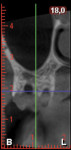

The treatment plan called for harvesting a cortico-cancellous autogenous bone block with its connective tissue and epithelium from the tuberosity. Therefore, a segmental cone-beam computed tomography (CBCT) scan was taken to assess the dimensions of the tuberosity and the position of the sinus floor and to avoid oroantral communication. Soft-tissue thickness was evaluated with a periodontal probe, and a square outline was drawn on the right tuberosity with a 15C blade, reaching the bone. Incisions were made 2 mm away from the lateral margins of the tuberosity and 1 mm away from the distal surface of the last molar. Incisions were designed perpendicularly to the coronal aspect of the tuberosity and slightly angulated from the outer part to the inner side of the bone. The graft was then harvested with a bone chisel and mallet (Figure 7).

After 4 months, the peri-implant soft tissues appeared healthy, and the probing depths ranged from 3 mm to 4 mm with no bleeding on probing. A digital impression was made, and the final implant-supported zirconia crown was delivered 2 weeks later. The bone around the implant head was radiographically stable at the 2-year follow-up, with only a slight sign of remodeling around the abutment connection (Figure 11 and Figure 12). The CBCT showed a buccal bone plate with 2 mm of thickness on the facial aspect of the implant, and no increase in gingival recession was noted (Figure 13).